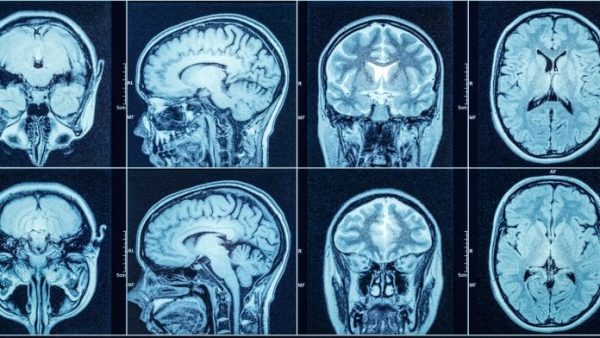

Αλγόριθμος που έμαθε να αναλύει μαγνητικές τομογραφίς αποκαλύπτει τα μοτίβα αλλοιώσεων που συνδέονται με διαφορετικές παθήσεις.